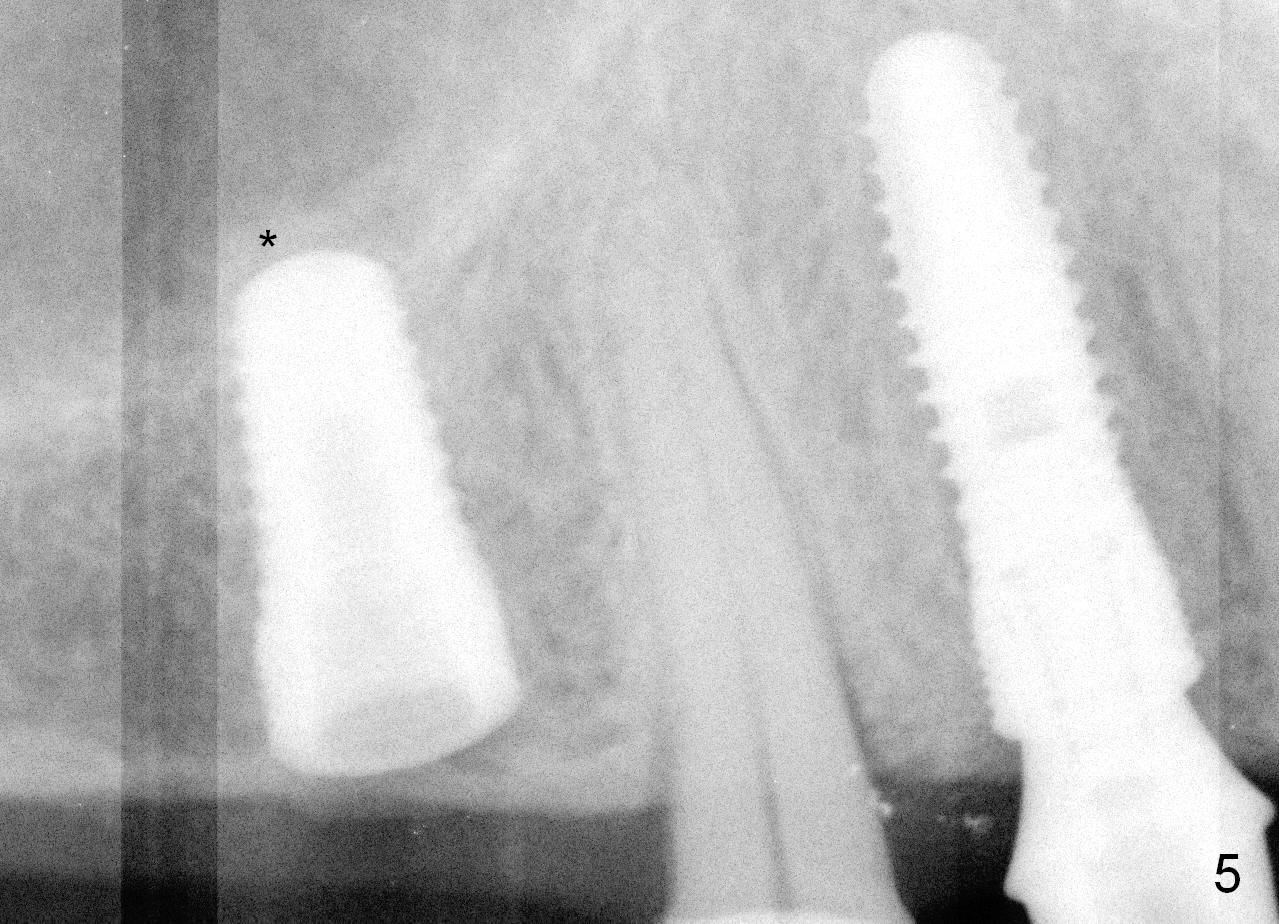

Both the teeth #30 and 31 are supraerupted. There is no restorative space for #2. So #3 implant will support the most distal crown. A 4 mm tissue punch is used, followed by a 2 mm pilot drill. Bone type is 3. A parallel pin shows that the trajectory needs to be adjusted (Fig.2). By the time a 4.5 mm tap is placed, the trajectory is within normal limit (Fig.3,4 T). A 5.3x10 mm implant is placed with insertion torque > 60 Ncm (Fig.5; *: sinus lift). After insertion of an abutment, an immediate provisional is fabricated with intention to prevent further supraeruption of the tooth #30 during #3 implant osteointegration.